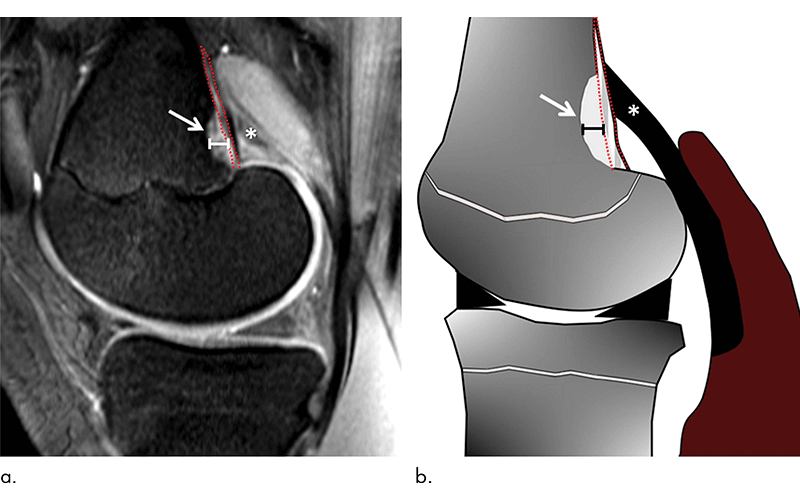

Routine knee MRI of adolescents often reveals tumor-like irregularities in the bone of the distal femur and these irregularities affect the cortical bone. For that reason, they are referred to as distal femoral cortical irregularities (DFCI). DFCI often lead to diagnostic uncertainty because they can be confused with more serious conditions like cancer or infection.

The researchers compared the knee MRIs of 105 youth competitive alpine skiers with those of 105 controls of the same age group collected from 2014 to 2019. They looked for the presence of DFCI at two tendon-bone attachment areas: the ones between the gastrocnemius—the major muscle of the calf—and the femur, and the ones between the adductor magnus muscle of the inner thigh and the femur.

DFCIs were observed at the attachment sites of tendons, predominantly at the inside head of the gastrocnemius muscle for both skiers and controls.

The most common theory behind the DFCI occurrence is that of a “tug lesion” as a result of repetitive mechanical stress where the tendons attach to the bone.